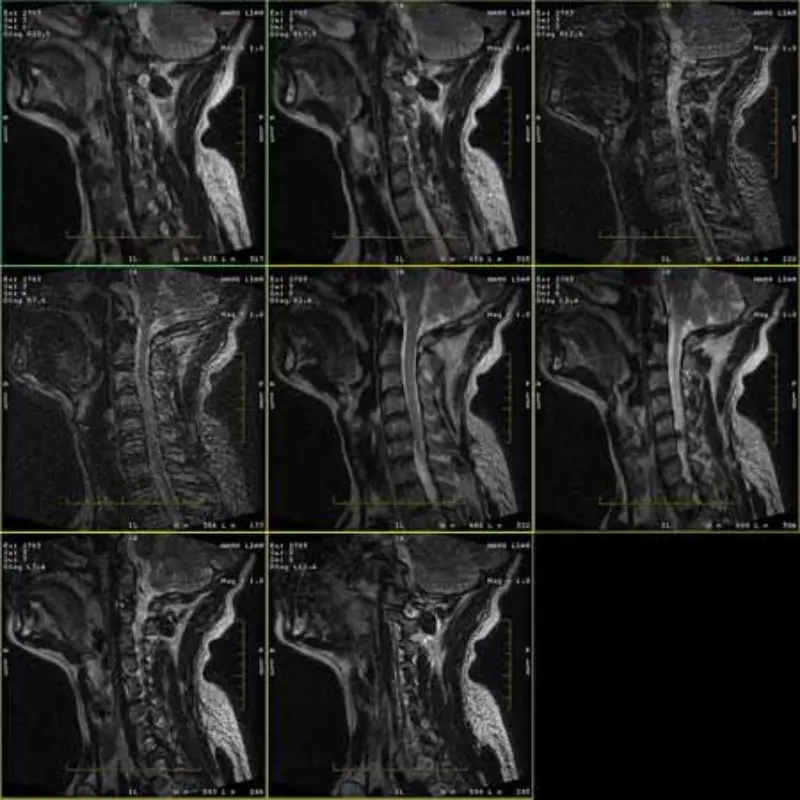

Bilderna av FRFSE- och GRE-protokollen har spökbilder och ibland visas låga SNR-bilder i en serie. Men SE-protokollbilder är normala.

Titta gärna bifoga bilder.